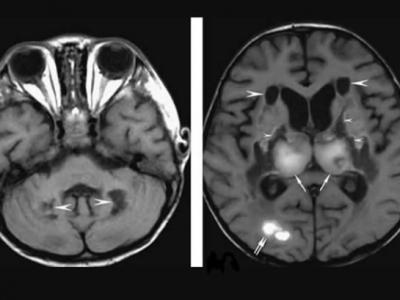

新冠肺炎患者现罕见并发症“急性坏死性脑

新冠肺炎患者现罕见并发症“急性坏死性脑病变” 精神错乱中风(神秘的地球uux.cn报...